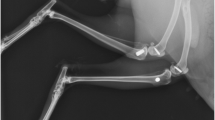

In order to assess the effect of the overall morphology on the bone healing ability, the studied morphologies were the Straumann tissue level, Klockner essential cone and implant prototype. The macrodesign of the Straumann tissue level implant—with its parallel-walls—features an 18° V-shaped thread with a 1.25 mm thread pitch and a 0.1 mm apex width. The morphology of the essential cone implant is characterised for being a conical implant with a 45° V-shaped thread, a 2.2 mm thread pitch with two inputs to increase the insertion speed and apex width of 0.21 mm. The morphology of the prototype implant is similar to the Klockner essential cone implant but differs in a 2-tenth reduction in the implant core, a sharper thread and the apex width is 0.12 mm (Fig. 1). The different implant morphologies were compared presenting the same surface treatment, which was the Shotblasting (Shot-blasted surface with alumina particles and acid attack with hydrochloric acid).

Regarding the macroscopic design, we compared three morphologies, mainly the Straumann tissue level, Klockner essential cone and a prototype design similar to the Klockner essential cone design having a common surface morphology in all cases. Overall, the thread pitch, the angle between the thread and the type of thread, were shown to influence the final outcome of the osseointegration process. The macrodesign of the Straumann tissue level implant—with its parallel-walls—features an 18° V-shaped thread with a 1.25 mm thread pitch and a 0.1 mm apex width. The morphology of the essential cone implant is characterised for being a conical implant with a 45° V-shaped thread, a 2.2 mm thread pitch with two inputs to increase the insertion speed and apex width of 0.21 mm. The morphology of the prototype implant is similar to the Klockner essential cone implant but differs in a 2-tenth reduction in the implant core, a sharper thread and the apex width is 0.12 mm (Fig. 1). Our hypothesis was that smaller angles allow better insertion of the implant hence reducing the tension concentration, which can negatively contribute to new bone formation [15].